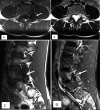

Figure 1.

13-year-old basketball player complaining of low back pain. (A) Axial T1 image demonstrates transversely oriented low signal (arrow) through the L5 pedicle and pars. (B) Axial T2 image demonstrates corresponding edema (arrow), confirmed on sagittal T1 (C) and STIR (D) sequences (arrows). Findings are consistent with unilateral stress fracture through the left pars interarticularis.

Figure 2.

16-year-old baseball pitcher with recent onset of low back pain. (A) Axial T1, (B) T2 and (C) sagittal STIR images demonstrates bone marrow edema (arrows) in the left L3 pedicle, consistent with non-displaced stress fracture.